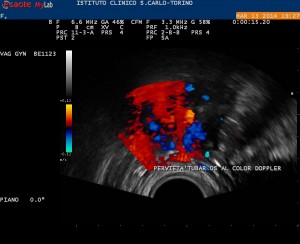

pervietà tubarica destra al color doppler